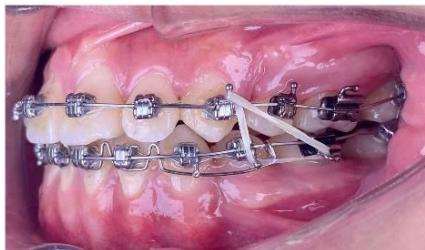

b) Anchorage Setup and Canine Retraction

After progression to a $0.019 \times 0.025$ stainless steel archwire, two interradicular mini-screws measuring $1.6 \times 10 \mathrm{~mm}$ were placed in the maxillary arch between the first and second premolars to reinforce posterior anchorage. Elastomeric chains delivering approximately $150 \mathrm{~g}$ of force were applied from the mini-screws to the maxillary canines to perform canine retraction using sliding mechanics [6,8]. In the mandibular arch, moderate anchorage was established using elastomeric

chains delivering approximately $150\mathrm{g}$ of force from the first molars to the canines.

Figure 6: Canine retraction on a $0.019 \times 0.025$ -inch stainless steel archwire using sliding mechanics

During the canine retraction phase, the patient wore intermaxillary elastics (3/16-inch, 3.5 oz) from the maxillary first molars to the mandibular first and second premolars to stabilize posterior occlusal interdigitation, as canine retraction using sliding mechanics tends to generate rotational moments and increases the risk of posterior occlusal disclusion [6,7].

From the rigid archwire stage onward, an ART torque spring was placed in the mandibular four-incisor region and maintained continuously throughout the canine retraction phase. The ART appliance functioned as an auxiliary torque spring, generating active positive torque to direct the incisor roots into cancellous bone and counteract the negative torque moments produced during space closure with force application below the center of resistance [6,9]. Studies on periodontal tissue response have demonstrated that light and continuous torque forces facilitate safe alveolar bone remodeling, particularly in regions where the incisor roots are positioned close to the labial cortical plate [22,23].